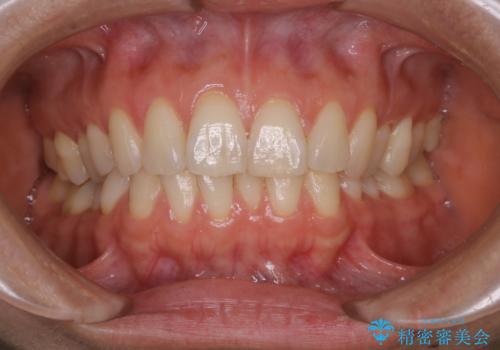

再矯正、後戻りを治したい、マウスピース矯正

途中で終わってしまったワイヤー治療もインビザラインで

抜歯矯正の後戻りが気になる インビザライン・ライトによる矯正治療